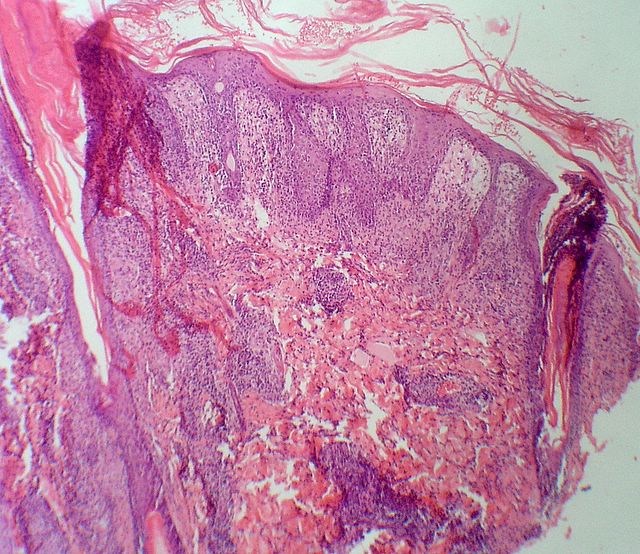

146 -- p1010014.jpg